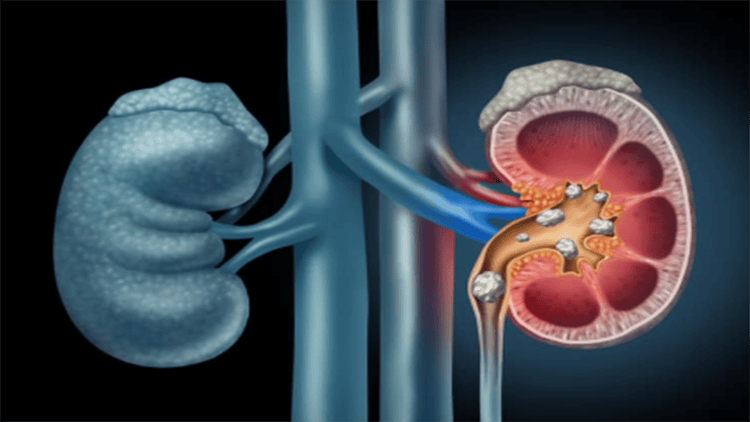

- Phát hiện các hẹp, tắc niệu quản do sỏi hoặc các nguyên nhân khác.

- Đánh giá phát hiện các hẹp, tắc niệu quản do sỏi hoặc các nguyên nhân khác.

Niệu quản bờ đều. Theo dõi thuốc đối quang trong niệu quản trên màn tăng sáng, khó khảo sát đoạn khúc nối bể thận-niệu quản và niệu quản bắt chéo động mạch chậu.

Hình thái đài bể thận niệu quản gần tương tự hình ảnh trên UIV hoặc rõ hơn.

Hình ảnh bất thường đường dẫn niệu gồm giãn, hẹp, tắc, hình lồi, hình khuyết, hình đè ép.

Ứ đọng thuốc đối quang khi có tắc đường dẫn niệu.